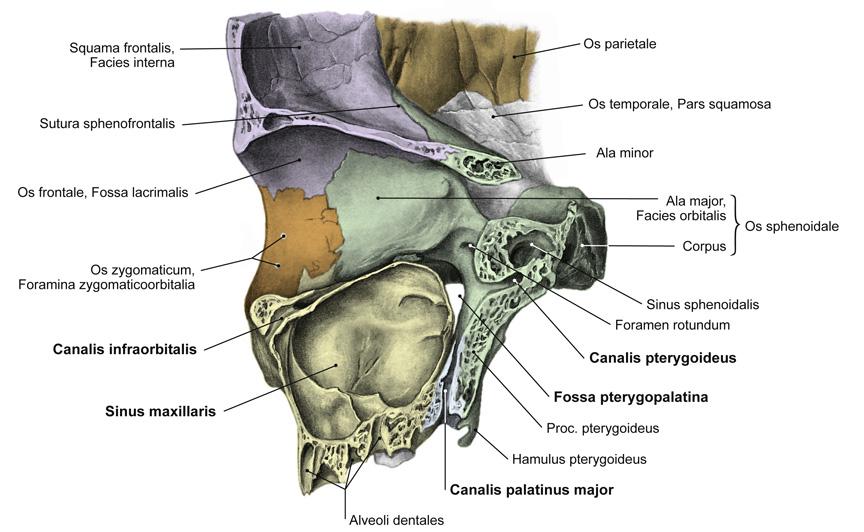

Fig 3.10a: a. maxillaris - sfenomaxillair deel

|

|